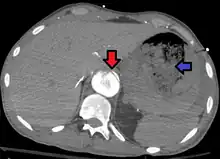

| Aorto enteric fistula and aortic dissection of the thoracic aorta. Arrow shows the flap in the aorta. Heterogeneity is blood in the stomach |